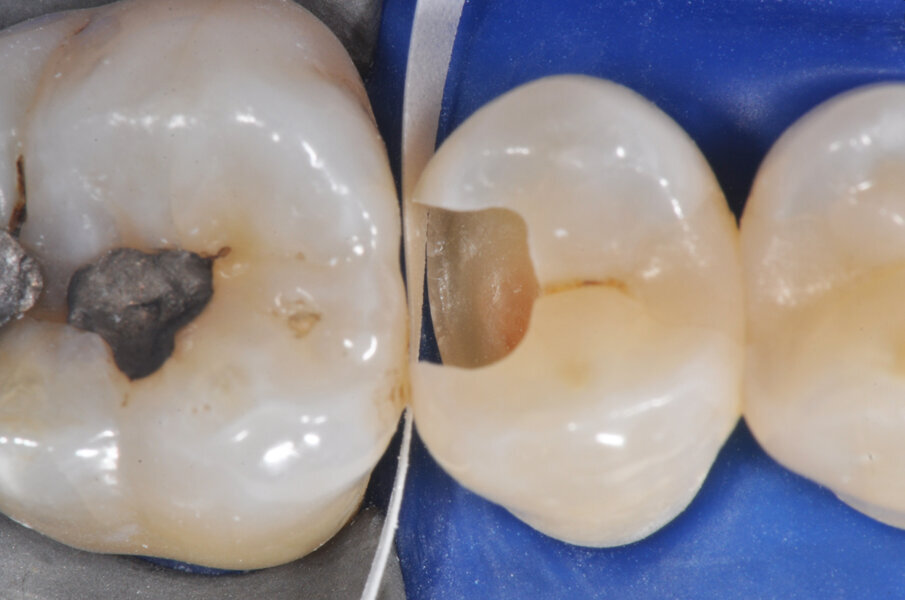

Viene posizionata una matrice Fusion FX175 e inserito un cuneo Fusion FXOR da vestibolare, per favorire la chiusura della matrice nell’angolo tra gradino cervicale e parete assio-pulpare vestibolare, resa difficile dalla rotazione dell’elemento 1.5 (Fig. 6). Si posiziona l’anello separatore FX400 - si noti il perfetto adattamento della matrice alle pareti assiali e al gradino cervicale. Quest’ultimo grazie soprattutto all’azione delle alette in silicone del cuneo (Fig. 7). Un’altra inquadratura evidenzia la profondità della cavità pulita (Fig. 8).